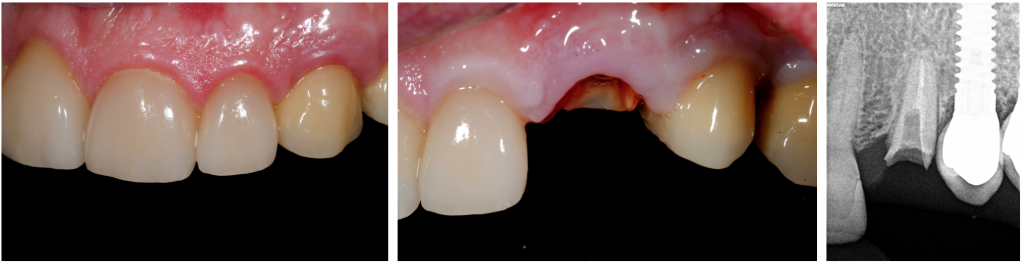

A 65-year-old male patient, with a fixed rehabilitation in #23 and implant-supported rehabilitation in teeth 24 and 25, presented with a complicated fracture on the left canine (#23).

A conservative extraction of tooth #23 with the anticipated subsequent resorption of the buccal tissues would have meant a far-reaching change of the aesthetics. So, the treatment plan implicated an immediate implant placement within the meaning of the socket-shield technique and flapless implant placement at the site of tooth #23 in order to maintain the initial gingival architecture.

Conservative extraction of the palatal root fragment was done with special forceps, and the socket was debrided gently and irrigated with normal saline.

Implant bed preparation at the palatal wall of the socket was performed, and a root-form implant (Klockner ®KL (4,2x12mm)) was placed according to the manufacturer's recommendations without contact with the shield.

The apicocoronal position of the implant platform was 1mm apical to the palatal marginal gingiva. The gap between the shield and implant surface was left to enable blood clot formation.

The final torque was 50nm, and we opted to do immediate non-functional loading through the splinting of provisional to the implant of teeth 24.